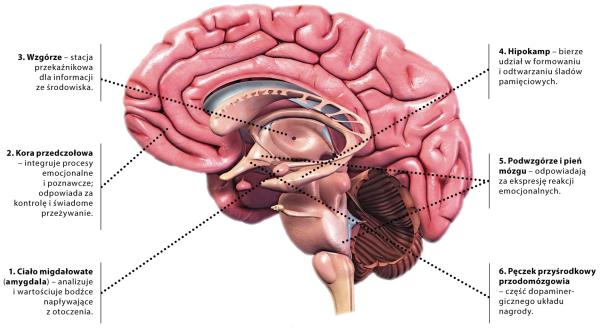

Depresja, euforia, miłość, skłonność do hazardu, łatwość uczenia się – wszystko to chemia. Chemia mózgu. Nasz temperament, nastrój, zdolności zależą w dużym stopniu od tego, jak mózg kręci rozmaitymi kurkami: upuści jednej substancji, dopuści drugiej.

Ludzka pamięć to nie jest jeden wielki magazyn wspomnień, ale sieć skomplikowanych systemów zmuszająca do wytężonej pracy niemal cały mózg.